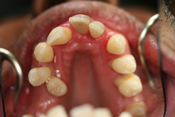

WORST TEETH Pictures from Warren Dentistry

This can happen to your teeth when proper Dental Hygiene is not practiced.

Patient 1